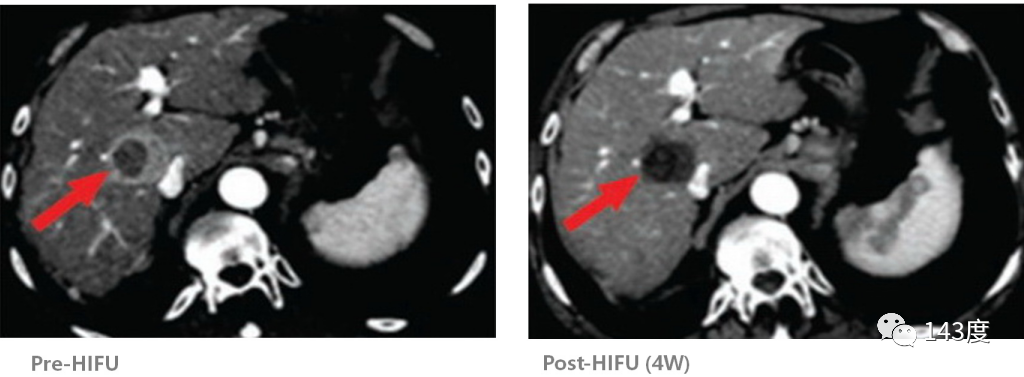

Liver Cancer Treatment Case 2:

Patient: Male, 52 years old, primary liver cancer

After radiofrequency ablation, residual tumor identified (tumor close to the inferior vena cava). Following a second HIFU treatment, complete ablation of the residual tumor achieved, with intact protection of the inferior vena cava.